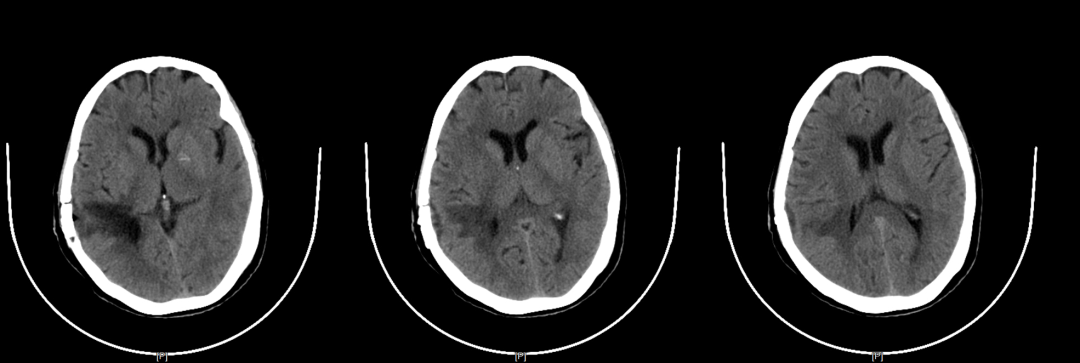

术后复查CT

图片

肿瘤切除满意,无出血渗血。目前,庄女士神志清除,生命体征平稳,肢体活动无障碍,已顺利出院。